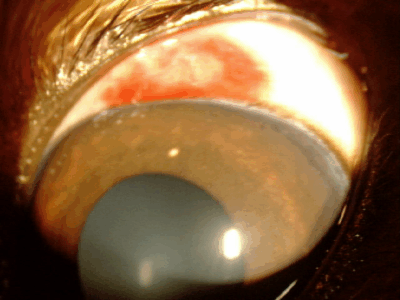

眼内出血

目の中で出血が起こり、黒目全体が赤く見えます。虹彩、毛様体、網膜、脈絡膜などの異常により起こることがあります。原因としてはぶどう膜炎、慢性緑内障、眼内腫瘍、網膜剥離などがあり、また全身性の高血圧で起こることもあります。失明につながる病気の可能性が高く、注意が必要です。